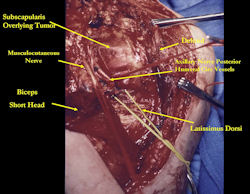

Examples of radical limb sparing surgeries for osteosarcomas in various anatomic locations (distal femur, proximal tibia, proximal humerus, scapula)

In each case, the tumor and bone from which it arose were resected. This required meticulous dissection, mobilization and preservation of adjacent pertinent neurovascular structures. In each case presented here, the defect was reconstructed with a special modular segmental tumor prosthesis. This also replaces the adjacent joint in many instances.

Proximal Humerus: Radical Limb Sparing Extra-Articular Resection and Prosethetic Reconstruction